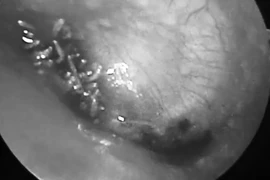

Kinh hãi: Giòi làm tổ lúc nhúc trong tai nam bệnh nhân